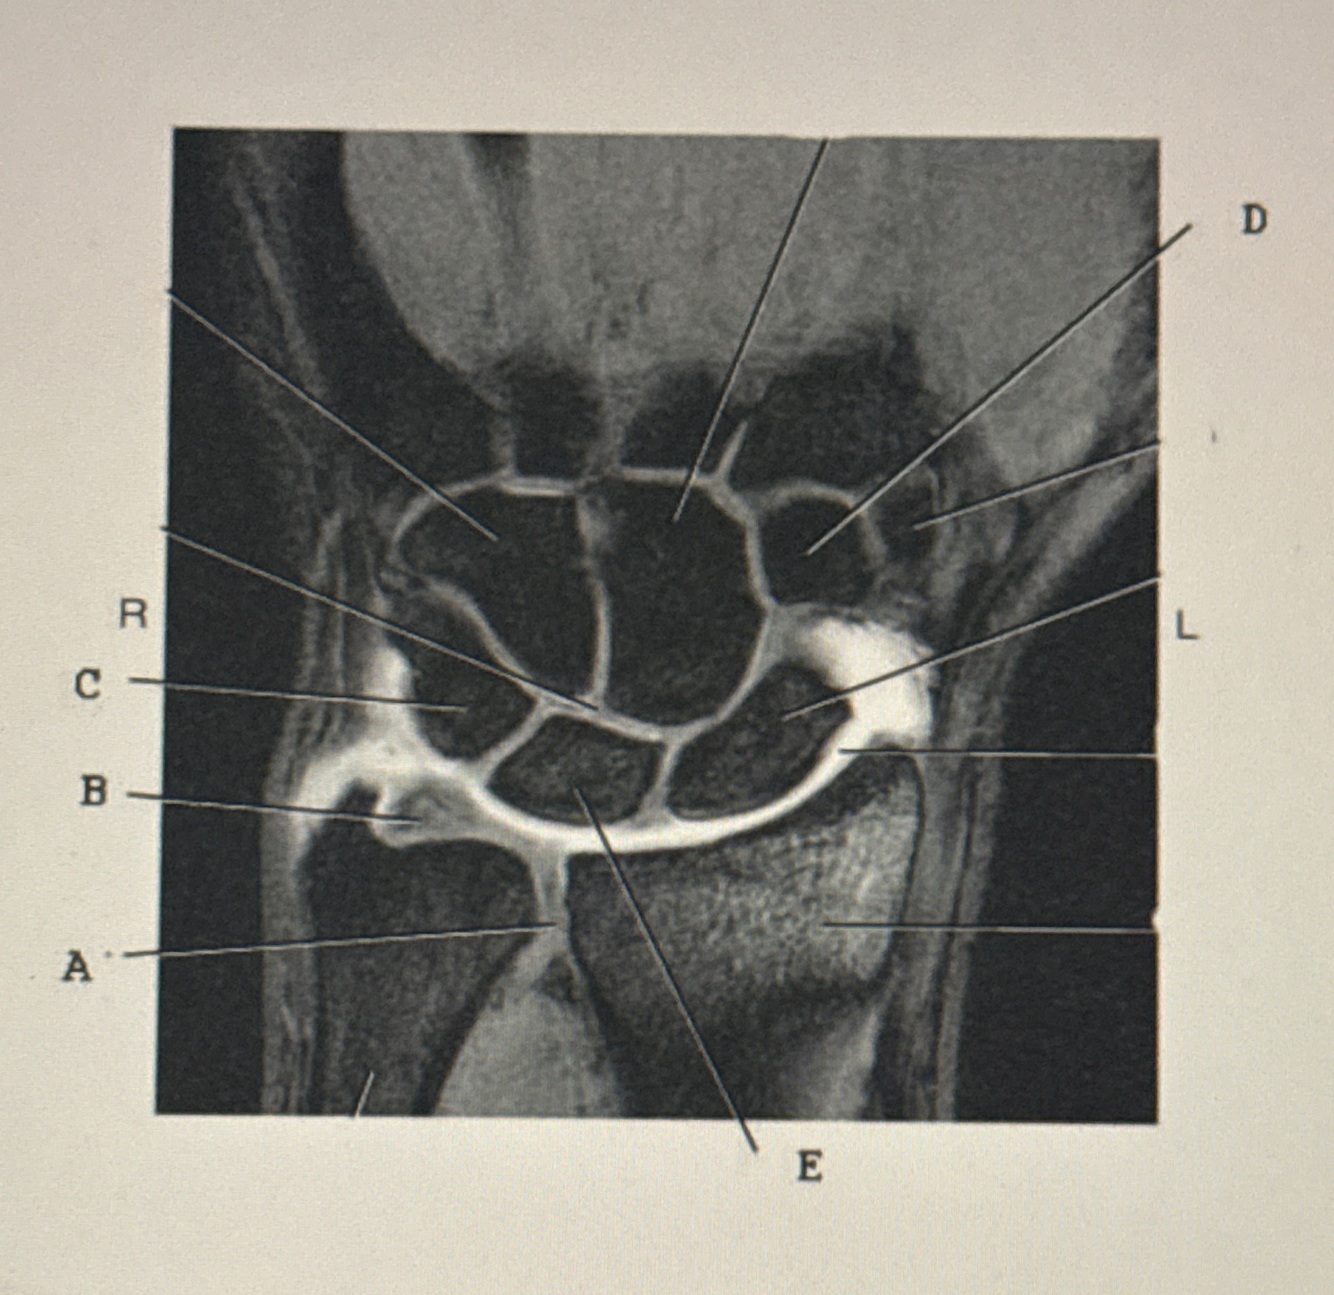

Q

1. Which letter points to the trapezoid

2. Which letter points to the TFCC 3. Which letter points to the lunate ?

A

1. D

2. B

3. E